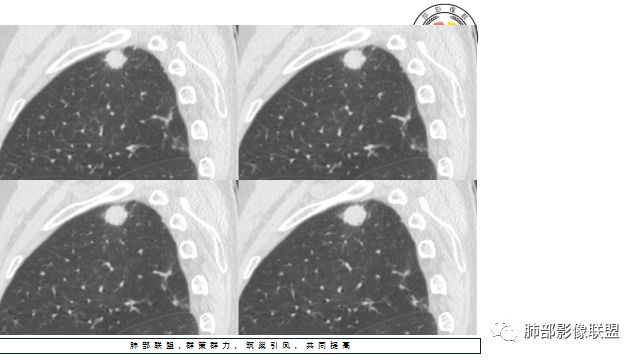

2.右肺尖类圆形结节影,边界清楚,未见明显分叶或深切迹,部分分边缘较平直,可见细长毛刺棘状突起,相邻胸膜增厚,未见胸膜凹陷。后段胸膜下见条索影及微小结节影。

相关血管未见脐凹,有限图像层面未能显示相关支气管情况。

4.增强扫描成明显环形强化,中央液化坏死,内壁清楚且较为规整。

好发于肺尖或尖后段胸膜下的密度不均的结节什么病最常见?结核!

小病灶常常出现空洞的什么病最常见?结核!

空洞内外壁都很清楚的什么病最常见?结核!

周围伴随小结节及条索影的什么病最常见?结核!